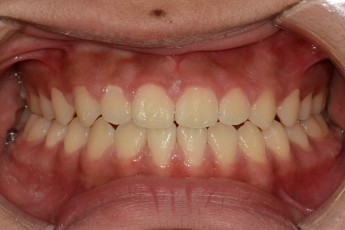

BEFORE & AFTER

- 덧니교정